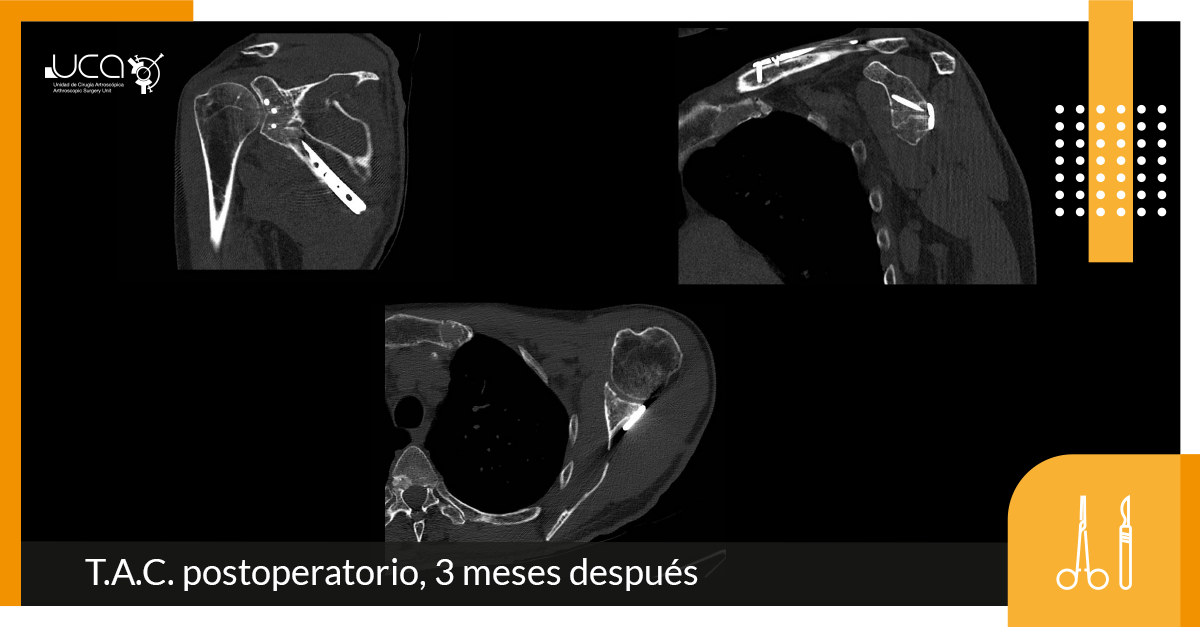

Abordaje posterior a pilar lateral escapular entre infraespinoso y redondo menor.

Se evidencia la fractura escapular conminuta con trazo glenoideo inferior.

Se realiza reducción y osteosíntesis con placa de neutralización anatómica de pilar lateral.